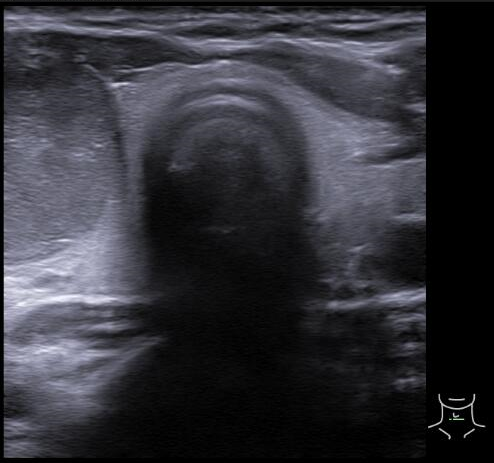

Ecografía tiroidea en AP: En lóbulo tiroideo derecho se aprecia nódulo: hipoecogénico, sólido, con márgenes definidos, sin focos ecogénicos, que presenta vascularización periférica, de morfología ovoide y de dimensiones 32x17x19 mm aproximadamente (CCxAPxT, más alto que ancho). Compatible con TIRADS 4.